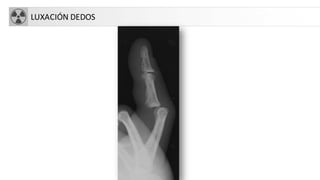

LUXACIÓN DEDOS

• Luxación: Pérdida completa de continuidad entre2 extremos óseos.

– Articulaciones interfalángicas.